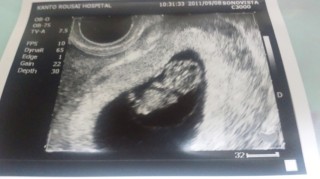

CRL 25.2mmでした。

頭と胴体がはっきり映り、人間らしい姿になってきたところですね。 エコーの白黒写真だけなのに、可愛い可愛いと親バカになってますf^_^;) まだまだつわりが続いていますが、辛い時は赤ちゃんも一緒に頑張ってるんだ!と励ましながら、なんとか乗り越えます(^ー^)ノ

手が顔の横にポンポンとあって二頭身の赤ちゃんを見て、可愛くて可愛くてニヤニヤが止まりませんでした(笑)

安定期にはいるまでは、不安は沢山ですがおちびちゃんを信じて共に頑張っていこうとゆう思いが、さらに強くなりました(^^)